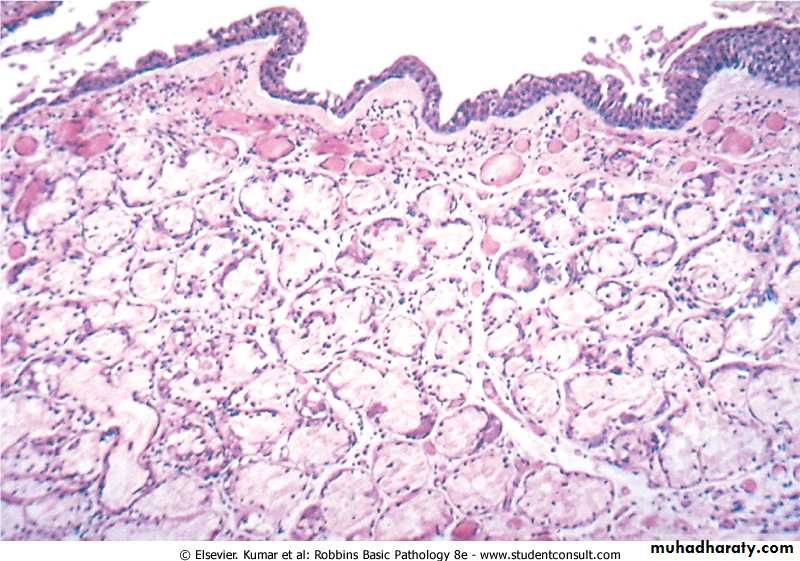

Emphysema

MorphologyThe diagnosis depend largely on the macroscopic appearance of the lung.

The lungs are pale, voluminous.

Histologically, thinning and destruction of alveolar walls creating large airspaces.

Loss of elastic tissue.

Reduced radial traction on the small airways.

Alveolar capillaries is diminished.

Fibrosis of respiratory bronchioles.

Accompanying bronchitis and bronchiolitis.

Gross Picture of Emphysema